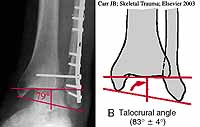

There may be soft tissue in the syndesmosis. Measure the talocrural angle tocalculate the amount of fibular shortening present, therefore the amount of lengthening needed. You need comparison films of the opposite side to do so. You may have to lengthen the fibula (use a 3.5 mm DCP not a 1/3 tubular), clear the tib-fib space and the medial clear space. It should not take much force to hold the tibial to the fibula, there is not suppposed to be anything in there. A femoral distractor may be of value in gaining length ( I have a scaled down version that uses 4.0mm ex fix pins).

What is the best way to judge fibular length? The talocrural angle has been suggested but here

it is practically normal and has been reported by Michelson et al as unreliable.

Maybe a better guide is the medial fibular prominence which should be at the level of the joint line (see Ed Rutledge OTA BFC lecture).

In this case, the medial fibular prominence appears to be at the tip of 2nd to most distal fibular screw and above the joint line.